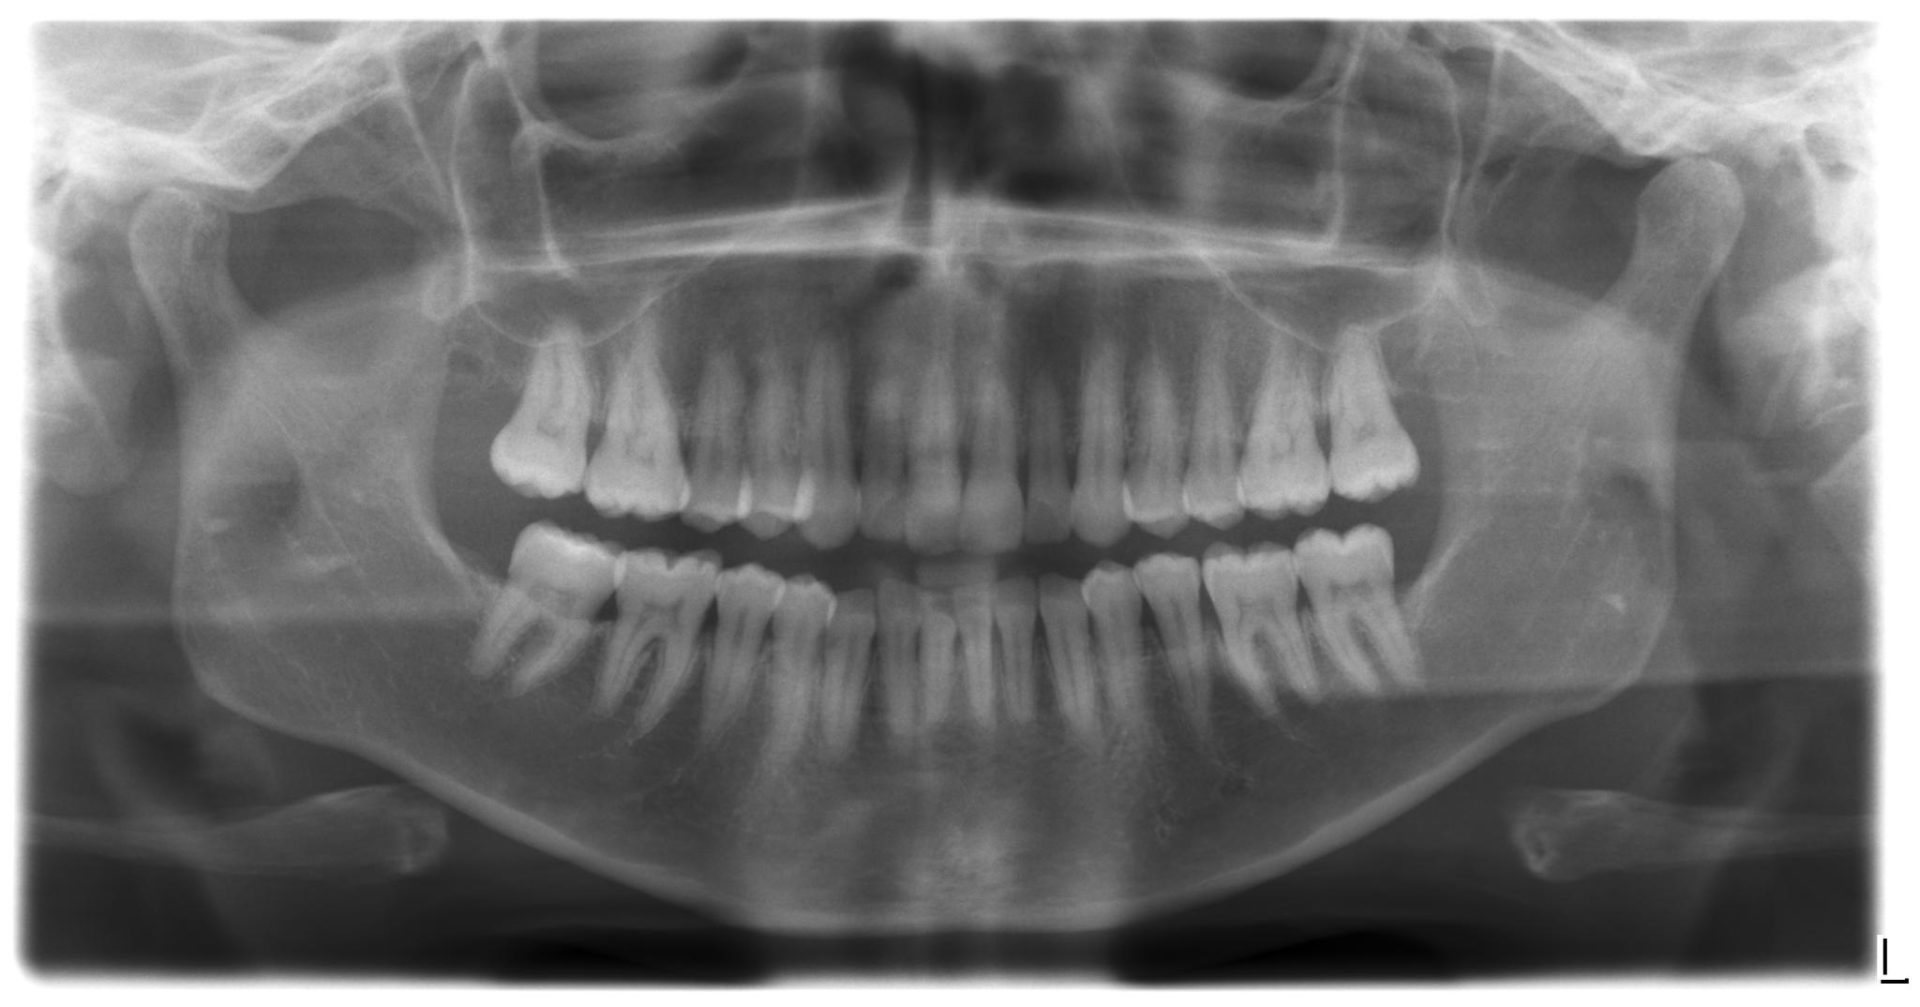

Notre système de radiologie au cabinet permet de faire, sur place, la radiographie panoramique numérisée indispensable pour vos contrôles ou bilan dentaire.

Nous disposons également de l’option 3D Cône Beam équivalent en qualité à un scanner mais beaucoup moins irradiant. Ces images permettent de nombreuses explorations

• Recherche de foyers infectieux ou kystes

• Recherche de canaux atypiques pour les traitements endodontiques (dévitalisation)

• Visualisation des impératifs anatomiques pour les dents de sagesses

• Planification de la position des implants dentaires

Le Cone Beam est considéré comme ayant été un progrès important pour l’imagerie médicaleUtilisant un faisceau conique de rayons X, il permet un examen performant des tissus minéralisés , mettant en évidence avec une excellente précision des lésions osseuses, fractures, infections, kystes et corps étrangers. En dentisterie, il permet la planification du positionnement des implants afin d’éviter les obstacles anatomiques.

Ces examens sont pris en charge par la sécurité sociale (excepté pour les implants dentaires).